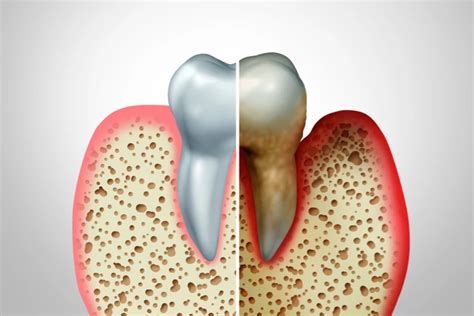

Pérdida de Hueso Dental

La pérdida de hueso dental es la principal consecuencia de la caída de dientes y conlleva empeoramiento de la funcionalidad de la mordida, con la consecuencia estética que implica. Este proceso de reabsorción ósea se produce en el hueso alveolar, encargado de sujetar toda la dentadura. Una vez que un diente se ha caído, el proceso de reabsorción se inicia tras 2 meses, aproximadamente.

El mejor tratamiento es la prevención. En casos de extracciones dentales, la solución más eficaz es la sustitución inmediata del diente a través de implantes. Mantén una buena rutina de higiene dental para eliminar las bacterias de la cavidad bucal. Ten en cuenta que una dieta saludable y un estilo de vida sanos estimulan tu sistema inmunológico.

En casos donde ya se ha perdido hueso, es posible que se necesite un injerto de hueso para proporcionar una base ósea suficiente para la colocación de implantes dentales.